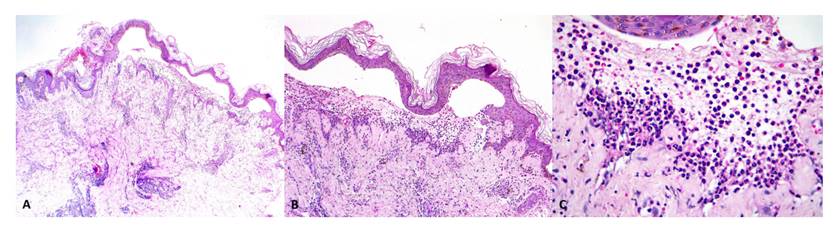

Ecocardiograma: fracción de eyección del ventrículo izquierdo (FEVI) 58 %, contractilidad conservada, no se observan vegetaciones. Se inició la cobertura antibiótica con vancomicina y se realizó un recambio del catéter de diálisis. Además, se practicó al paciente una biopsia de piel con resultado histopatológico de dermatosis ampollar subepidérmica (Figura 3 A, B) con numerosos neutrófilos (Figura 3 C), que se visualizan a mayor aumento (X40).

Figura 3 Ampollas subepidérmicas (A) HE, X2.5 y (B) HE, X4. (C) Neutrófilos dispuestos de manera dispersa en la dermis superficial (HE, X40).

En la histopatología se observa como una formación de ampollas subepidérmicas con infiltrado predominante de neutrófilos en la dermis superior, con presencia de microabscesos en la dermis papilar e infiltrado de neutrófilos en banda; también se puede observar fibrina y grandes depósitos de mucina en la dermis reticular 11-13. Además, se ha descrito un incremento gradual de la transcripción de neutrófilos durante la progresión a nefritis activa, lo que explicaría la asociación entre LESA y nefritis lúpica 8. En la inmunofluorescencia directa se observan depósitos lineales o granulares de Ig G (con Ig A o Ig G o sin ellas) y depósitos de complemento en la zona de la membrana basal 1,12. En nuestro caso, la histopatología coincidió con lo descrito en anteriores reportes de casos.